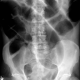

Pasien lansia, wanita 81 tahun, dengan riwayat stroke dan mobilisasi terbatas. Datang dengan keluhan nyeri perut, kembung, dan obstipasi selama 3 hari. Hasil rontgen abdomen terlampir. Menurut sejawat, apa diagnosisnya dan apa tindakan yang diperlukan ya, Dok?

Halo dok.. izin komen..Untuk pasien dengan terbatas mobilisasi karena stroke.. ada pertimbangan terjadinya paralitik bisa karena ada masalah di otak atau terjadinya masalah d tulang belakang.. mirip mirip tidak bisa BAK karena neurogenic bladder.. ini yang tipe usus menjadi malas kontraksiMemang gambaran terlihat seperti volvulus sigmoid/cofee bean sign.. ada juga kemungkinan arah ke situ.. So baiknya d periksa langsung ke kami dokter spesialis bedah..

Kayak gambaran sigmoid volvulus ya dok..

Benar dok, seperti sigmoid volvulus ya

Gas semua itu, ya. Apakah perlu laparotomy?